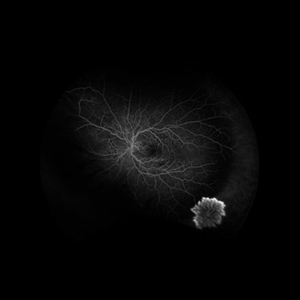

PDR with NVE (Periphery) PDR with NVE (Periphery)Jul 23 2024 by Ashley Phillips FA photo of a 62 y/o male with PDR and NVE (periphery) Photographer: Ashley Phillips Imaging device: Optos-California Condition/keywords: Neovascularisation elsewhere (NVE), PDR